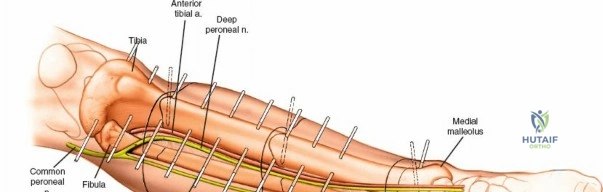

This topic focuses on Key Approaches for External Fixation: Humerus, Radius, Ulna, Wrist, Approaches for external fixation involve anchoring pins or wires into bones like the humerus, radius, ulna, pelvis, femur, tibia, fibula, and ankle. These fixators provide stability for open fractures, polytrauma, or temporary immobilization when soft tissues are severely injured. Pin placement is critical to avoid nerve/vessel damage and ensure effective treatment.

External fixation remains a cornerstone in the management of complex orthopedic trauma, particularly in scenarios involving severe soft tissue compromise, polytrauma, and bone loss. Although a wide variety of external fixators can be constructed, they all fundamentally consist of only two elements: pins or wires inserted into the bone to anchor the device to the skeleton, and external connectors (bars or rings) to provide stability.

Skeletal pins are usually inserted through small open incisions in the skin in a controlled fashion, with careful dissection of the soft tissues. Exceptions occur where nerves are in close proximity to pin placement, such as the distal third of the radius, where a larger mini-open approach is mandatory. Studies of cross-sectional anatomy in cadaveric material reveal a large number of possible pin placements for any given bone in any given position, but clinical application restricts these to validated "safe zones."

There are three main uses for external fixators in the upper extremity. First, fixators may be used as a temporary method of immobilizing a fracture in cases where the soft tissues are so injured that immediate open surgery is impossible. These fixators frequently span joints, and the pins used are ideally placed outside the zone of injury so that they do not interfere with subsequent definitive surgery. Second, fixators may be used as a way of stabilizing long bone fractures in cases of polytrauma, adhering to the principles of Damage Control Orthopedics. Finally, the most common indication for the use of an external fixator is in open fractures. These injuries usually are associated with fracture displacement, and the normal anatomy frequently is distorted. When skeletal pins are used, nerves and vessels may be damaged as they course down the limb. Distortion of the normal anatomy or normal anatomic variation may make apparently safe routes hazardous.